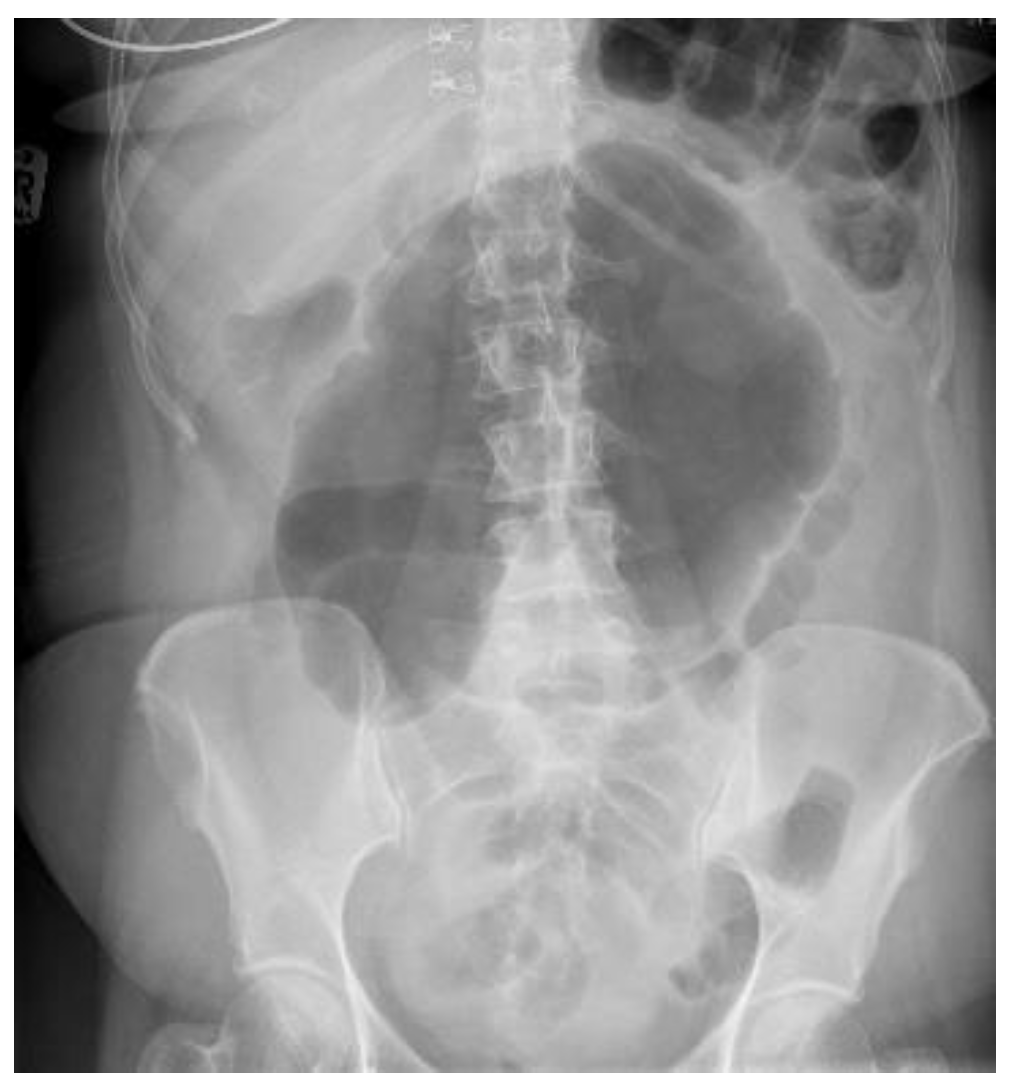

4.4.1. Conventional Radiography

| Abdominal radiograph | 11 (68.75%) | Five patients had CT as the only imaging. |

| Non-specific bowel loops/SBO | 5 (46%) | |

| Classical single loop of large bowel | 6 (54%) | |